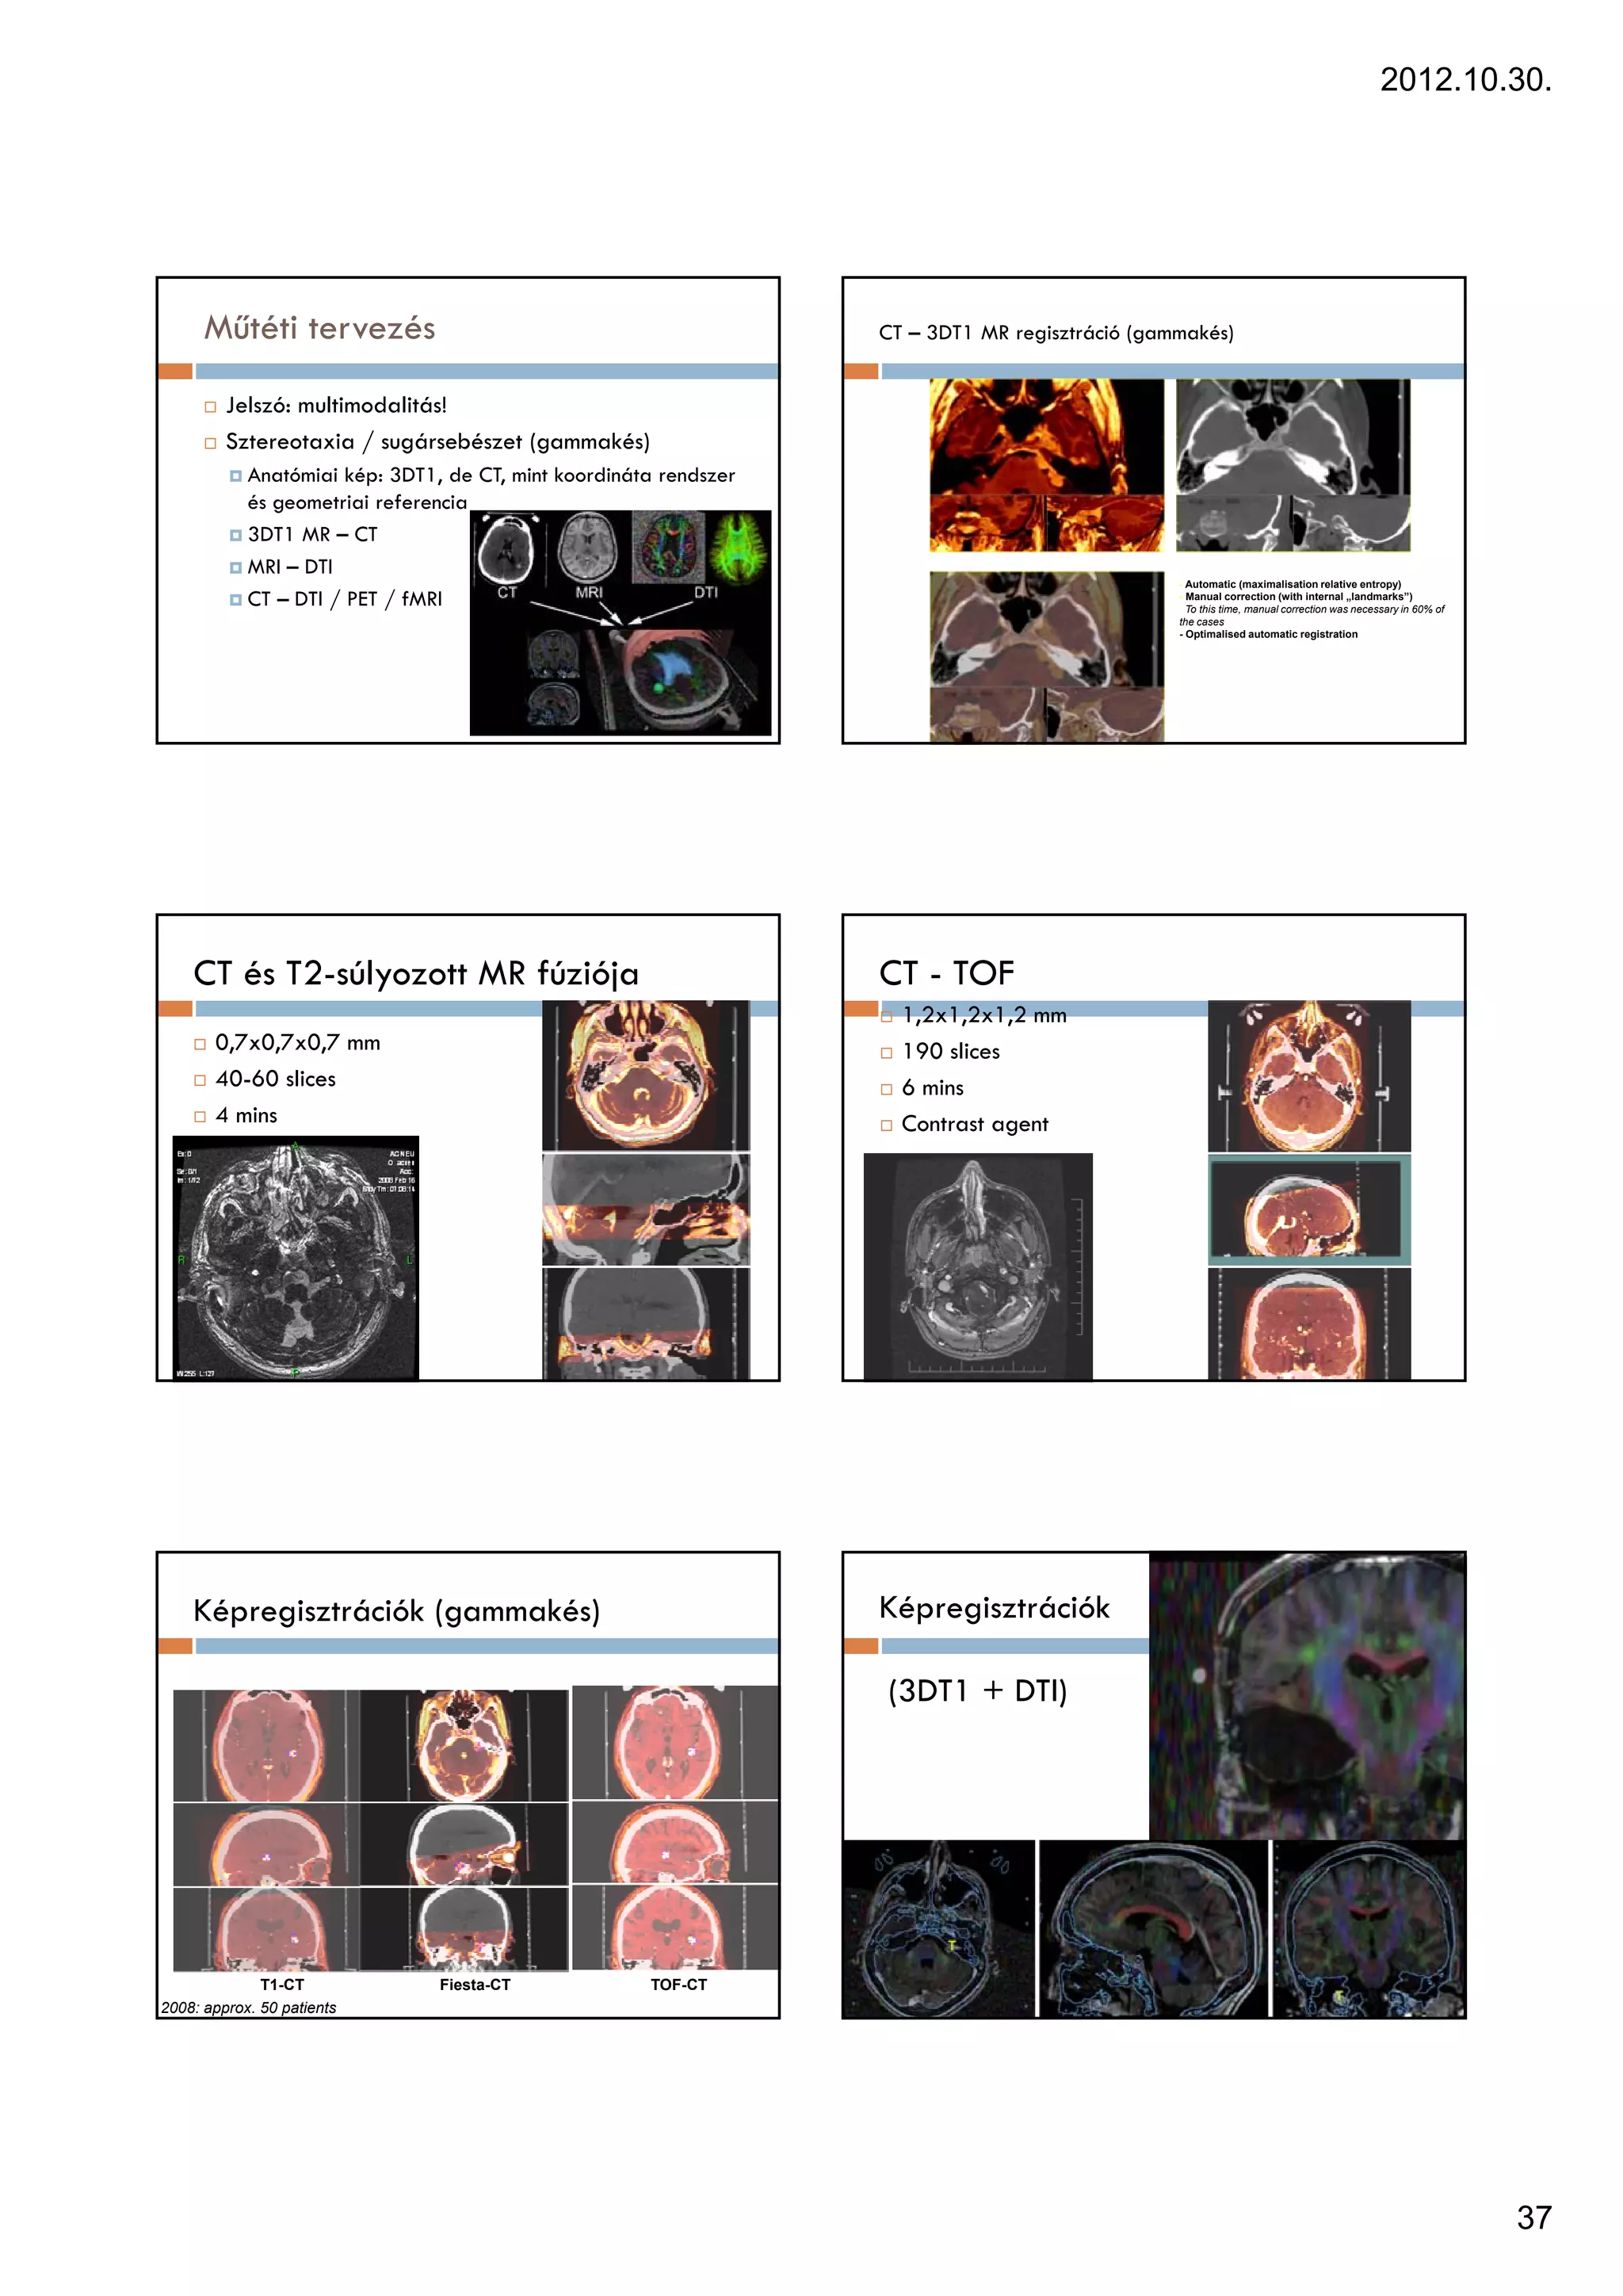

Műtéti tervezés                                              CT – 3DT1 MR regisztráció (gammakés)

Jelszó: multimodalitás!

Sztereotaxia / sugársebészet (gammakés)

Anatómiai kép: 3DT1, de CT, mint koordináta rendszer

és geometriai referencia

3DT1 MR – CT

MRI – DTI

- Automatic (maximalisation relative entropy)

CT – DTI / PET / fMRI                                                                - Manual correction (with internal „landmarks”)

To this time, manual correction was necessary in 60% of

the cases

- Optimalised automatic registration

CT és T2-súlyozott MR fúziója                                  CT - TOF

1,2x1,2x1,2 mm

0,7x0,7x0,7 mm                                                190 slices

40-60 slices                                                  6 mins

4 mins                                                        Contrast agent

Képregisztrációk (gammakés)                                    Képregisztrációk

(3DT1 + DTI)

T1-CT             Fiesta-CT             TOF-CT

2008: approx. 50 patients